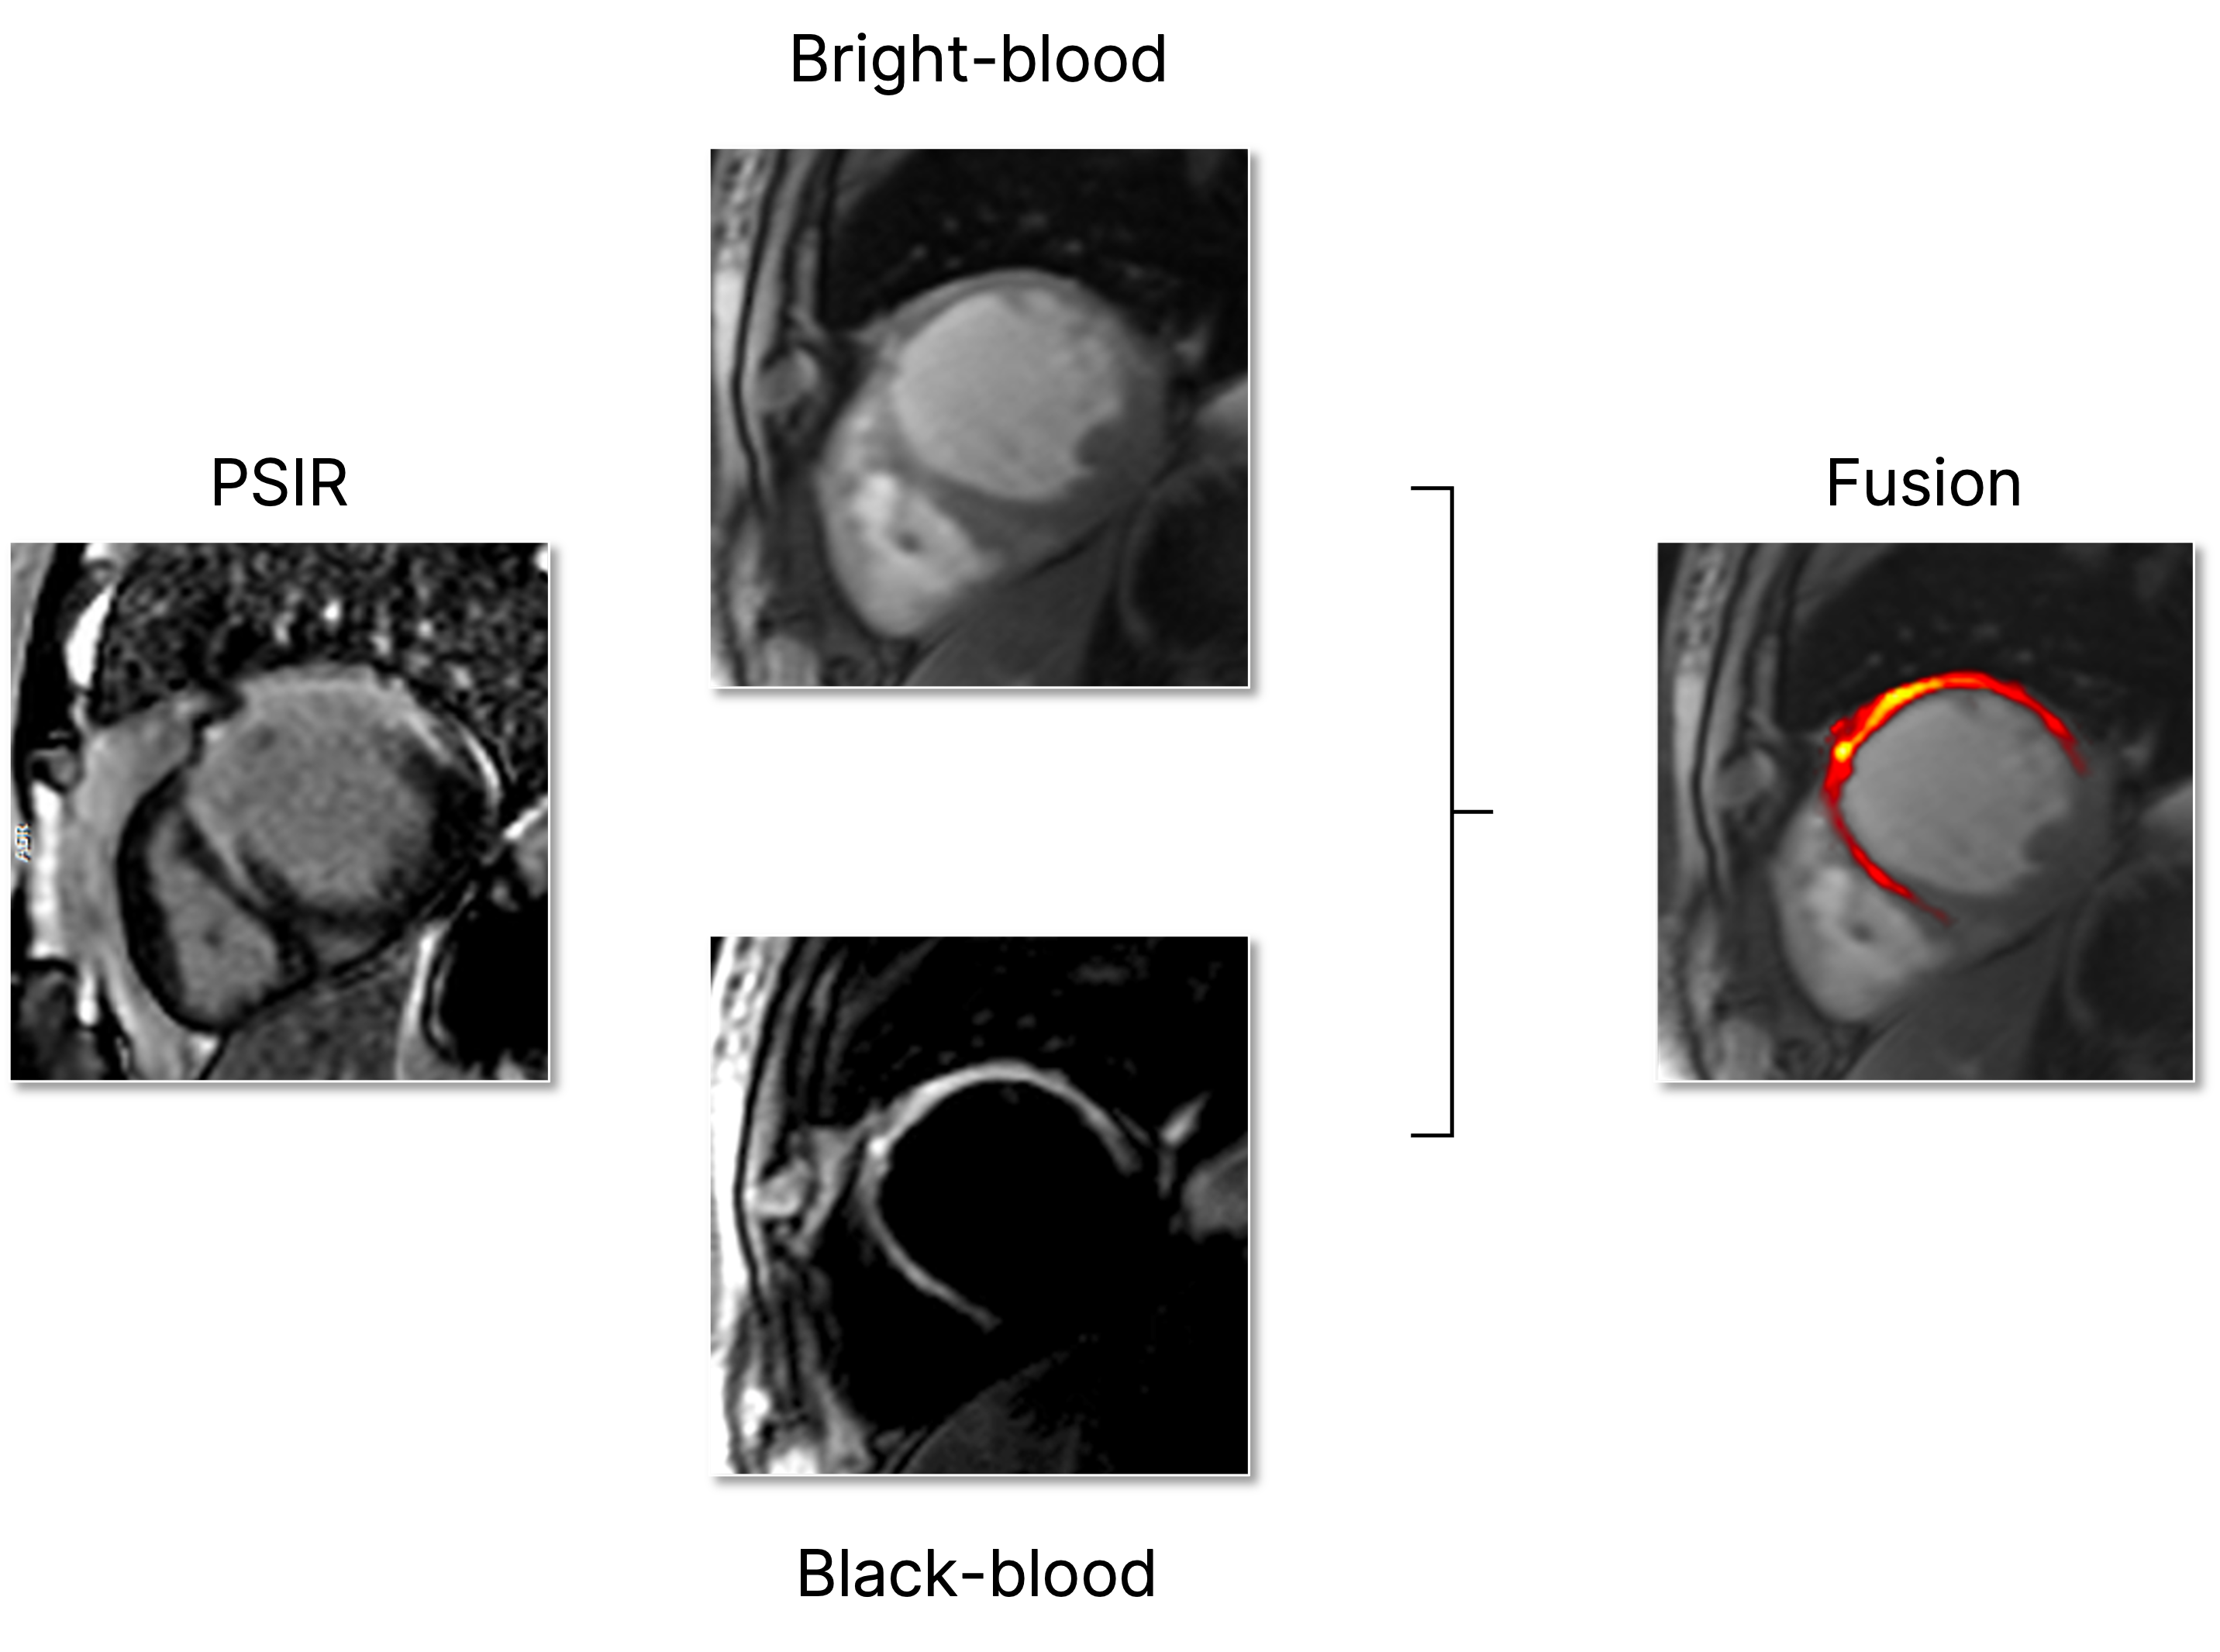

Joint bright- and black-blood late gadolinium enhancement imaging for improved myocardial scar visualization.

Automated contrast selection

Fully automated inversion time selection for enhanced scar visualization and detection.